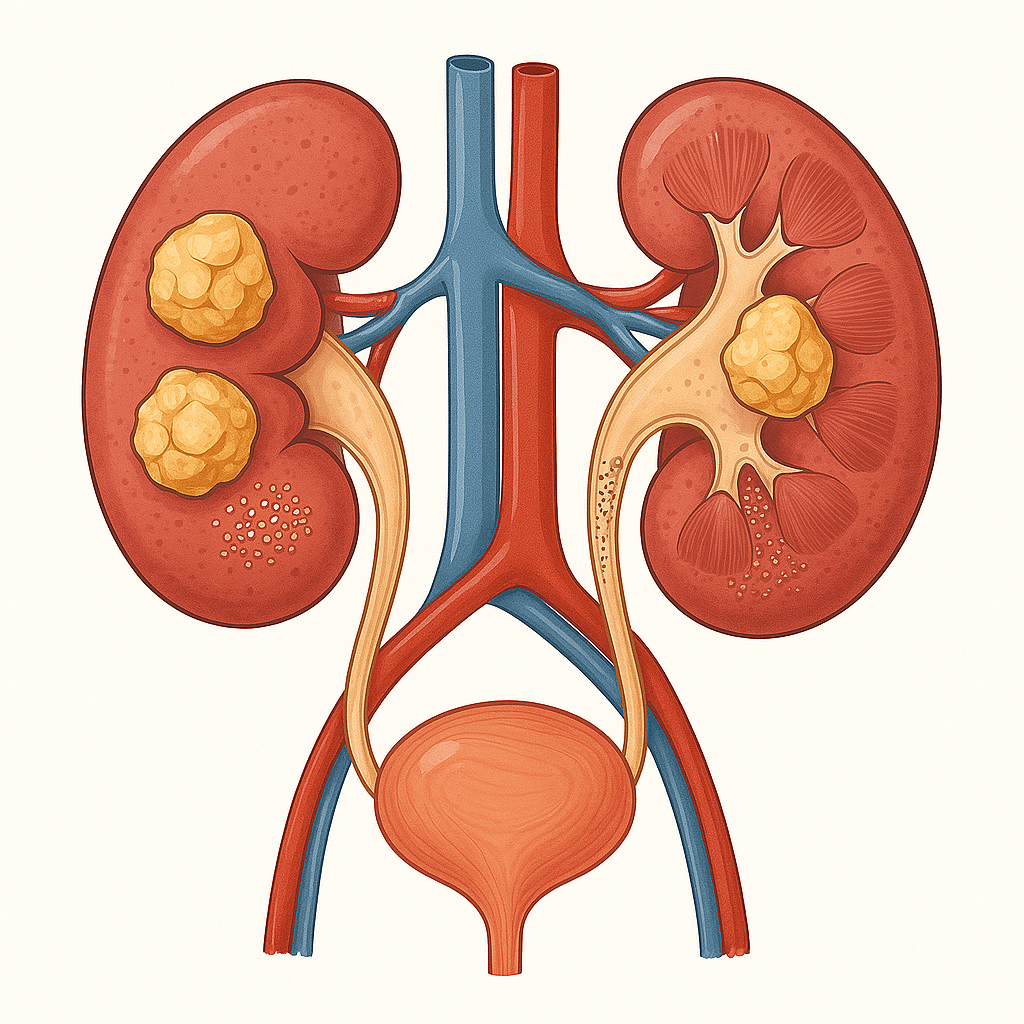

Камъни и песъчинки в бъбреците

(уролитиаза)

📌 Корен Гръмотрън

✅ Уриноотделяне и бъбречно здраве:

👉 Има диуретично и противовъзпалително действие, подпомага отделянето на урина и изчистване на песъчинки.